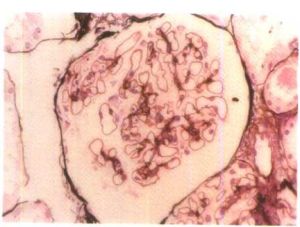

(3)Lange等用螢光抗體法曾發現在腎小球系膜細胞中及腎小球基底膜上有鏈球菌抗原,在電鏡下觀察到腎小球基底膜與上皮細胞足突之間有緻密的塊狀駝峰樣物存在,內含免疫複合物及補體。患者腎小球上IgG及C3呈顆粒狀沉著。患者腎小球中有補體沉著、多形核白細胞及單核細胞浸潤,表明這三類炎症介導物質進一步促進了病變的發展巨噬細胞增殖在病變發展中也起重要作用。NF-κB核轉錄因子在免疫系統的細胞中起關鍵性作用,NF-κB調節涉及腎小球腎炎發病機制中許多致炎性細胞因子和細胞黏附分子基因轉錄。

妊娠合併急性腎小球腎炎大部分患者恢復較快,上述變化在短期內可完全消失,少數患者腎小球毛細血管蒂部間質細胞增殖及沉積物消失需歷時數月或更長,少數患者病變繼續發展,腎小球囊上皮細胞增殖較為明顯並可與腎小球毛細血管叢粘連局部形成新月體,巨噬細胞增殖也可形成新月體,逐漸轉入慢性。在嚴重的病例,進球小動脈及腎小球毛細血管可發生纖維素樣壞死及血栓形成,或上皮細胞和巨噬細胞顯著增殖,可轉變為新月體性腎炎,短期導致腎功能衰竭。

病變主要在腎小球引起血尿、蛋白尿、腎小球濾過率下降,導致鈉、水瀦留,而腎小管功能基本正常,表現為水腫、高血壓,嚴重時可致左心衰竭及高血壓腦病。